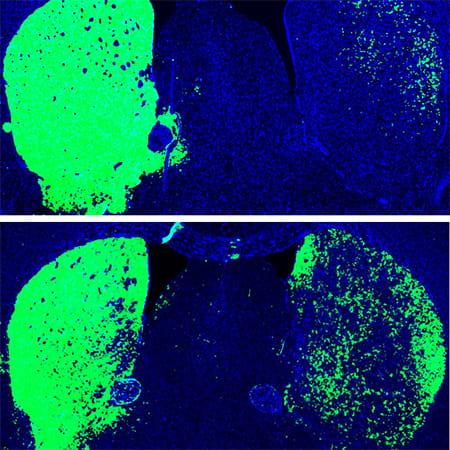

More recently, Fu and Hao Qian, PhD, another postdoctoral researcher in his lab, took the finding a big step forward, applying it in what could one day be a new therapeutic approach for Parkinson's disease and other neurodegenerative diseases. Just a single treatment to inhibit PTB in mice converted native astrocytes, star-shaped support cells of the brain, into neurons that produce the neurotransmitter dopamine. As a result, the mice's Parkinson's disease symptoms disappeared.

The researchers administered the PTB antisense oligonucleotide treatment directly to the mouse's midbrain, which is responsible for regulating motor control and reward behaviors, and the part of the brain that typically loses dopamine-producing neurons in Parkinson's disease. A control group of mice received mock treatment with an empty virus or an irrelevant antisense sequence.

In the treated mice, a small subset of astrocytes converted to neurons, increasing the number of neurons by approximately 30 percent. Dopamine levels were restored to a level comparable to that in normal mice. What's more, the neurons grew and sent their processes into other parts of brain. There was no change in the control mice.